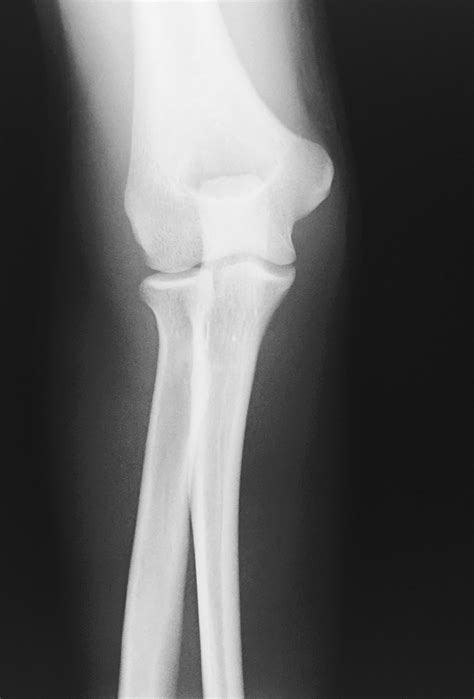

Elbow Joint Effusion occurs when there is an abnormal accumulation of fluid within the joint capsule. The elbow joint is lined with a thin membrane called the synovium, which produces a small amount of fluid to lubricate the cartilage and allow for smooth movement. When the joint is irritated—due to trauma, infection, or chronic inflammatory diseases—the synovium overproduces this fluid, leading to swelling, stiffness, and restricted range of motion.

Because the elbow joint capsule is relatively tight, even a small increase in fluid volume can cause significant pressure. This pressure is often what leads to the sharp pain or aching sensation patients report. It is important to distinguish effusion from bursitis, as the former occurs inside the joint space, whereas bursitis typically occurs in the bursa sac outside the joint.

Anatomical representation of the elbow joint

• Traumatic Injury: Fractures (such as a radial head fracture) or dislocations are the most common causes. The body triggers an inflammatory response to protect the area.

• elbow joint effusion x ray